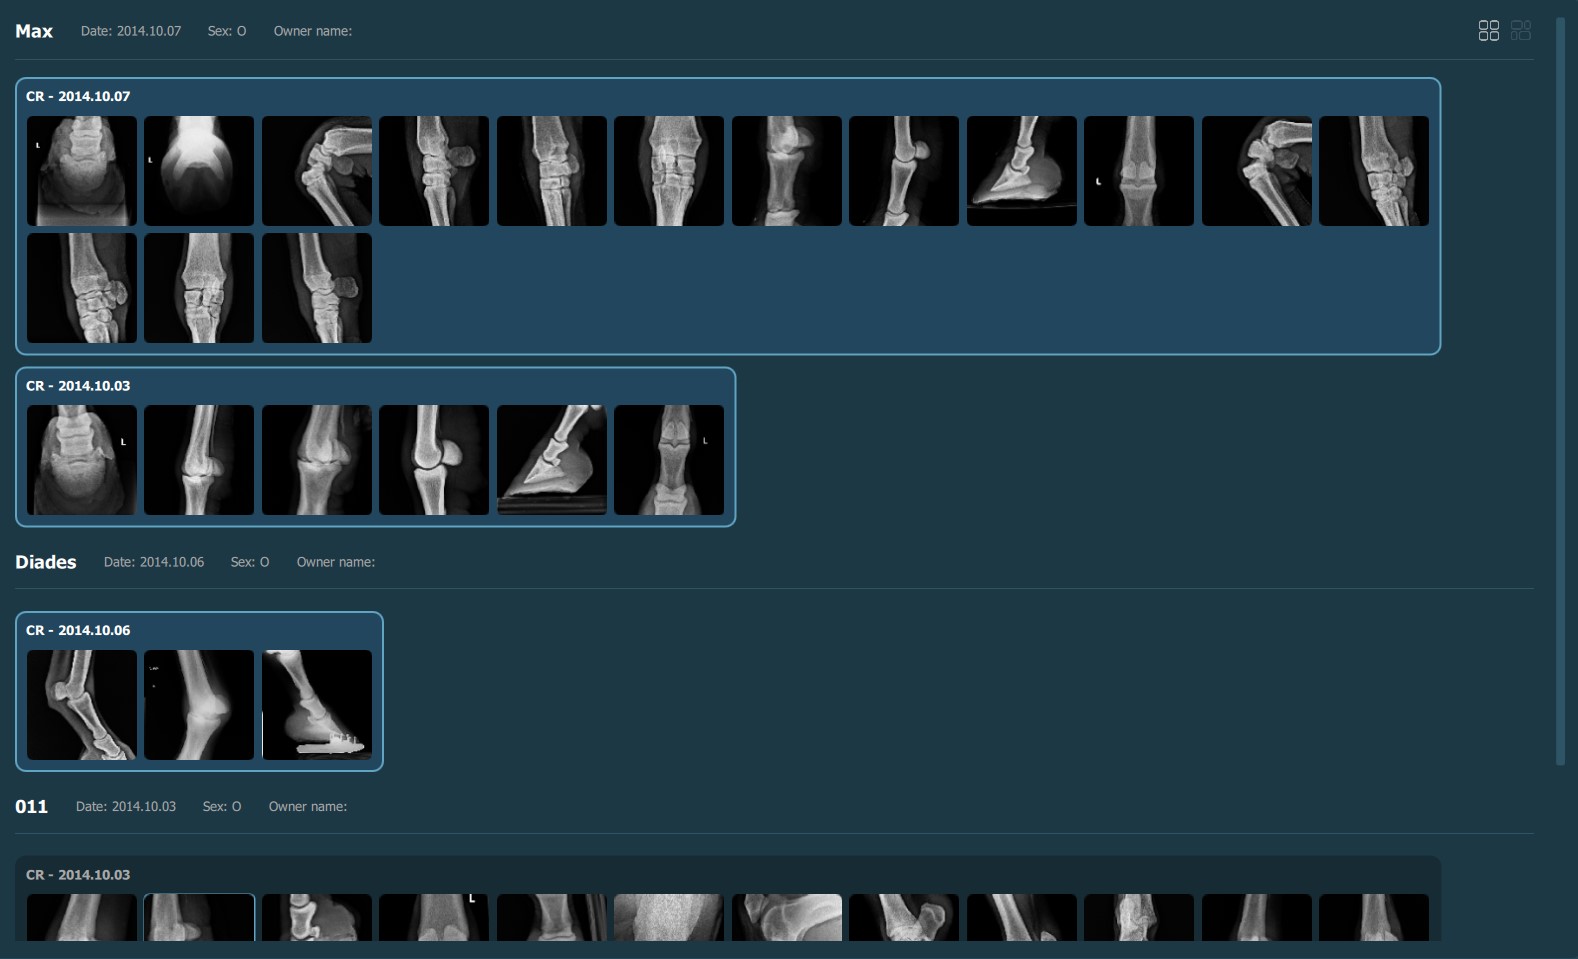

Selecting a patient, study, or series from the Study List opens them and their contents in the Preview Pane, located on the right side of the Study Browser window. In the Preview Pane, the items are separated into sections based on their patient information.

The heading of each section shows the patient name, the latest related study date, patient sex, and owner name. Studies are shown as image groups containing the series as image previews. Each study is highlighted by its modality and date. To view the series description of each series, hover over the desired image preview.

Similar to the selection in the Study List, users have the ability to select patients, studies, or individual series. A highlighted selection in the Preview Pane indicates the active selection in the Study List.

The Preview Pane can also be used to extend or narrow down the selection from the Study List. To select/deselect items in the Preview Pane simply press on them with the mouse.

Selected patient (all studies belonging to the patient are also selected):

Selected individual studies:

Selected individual series/images: